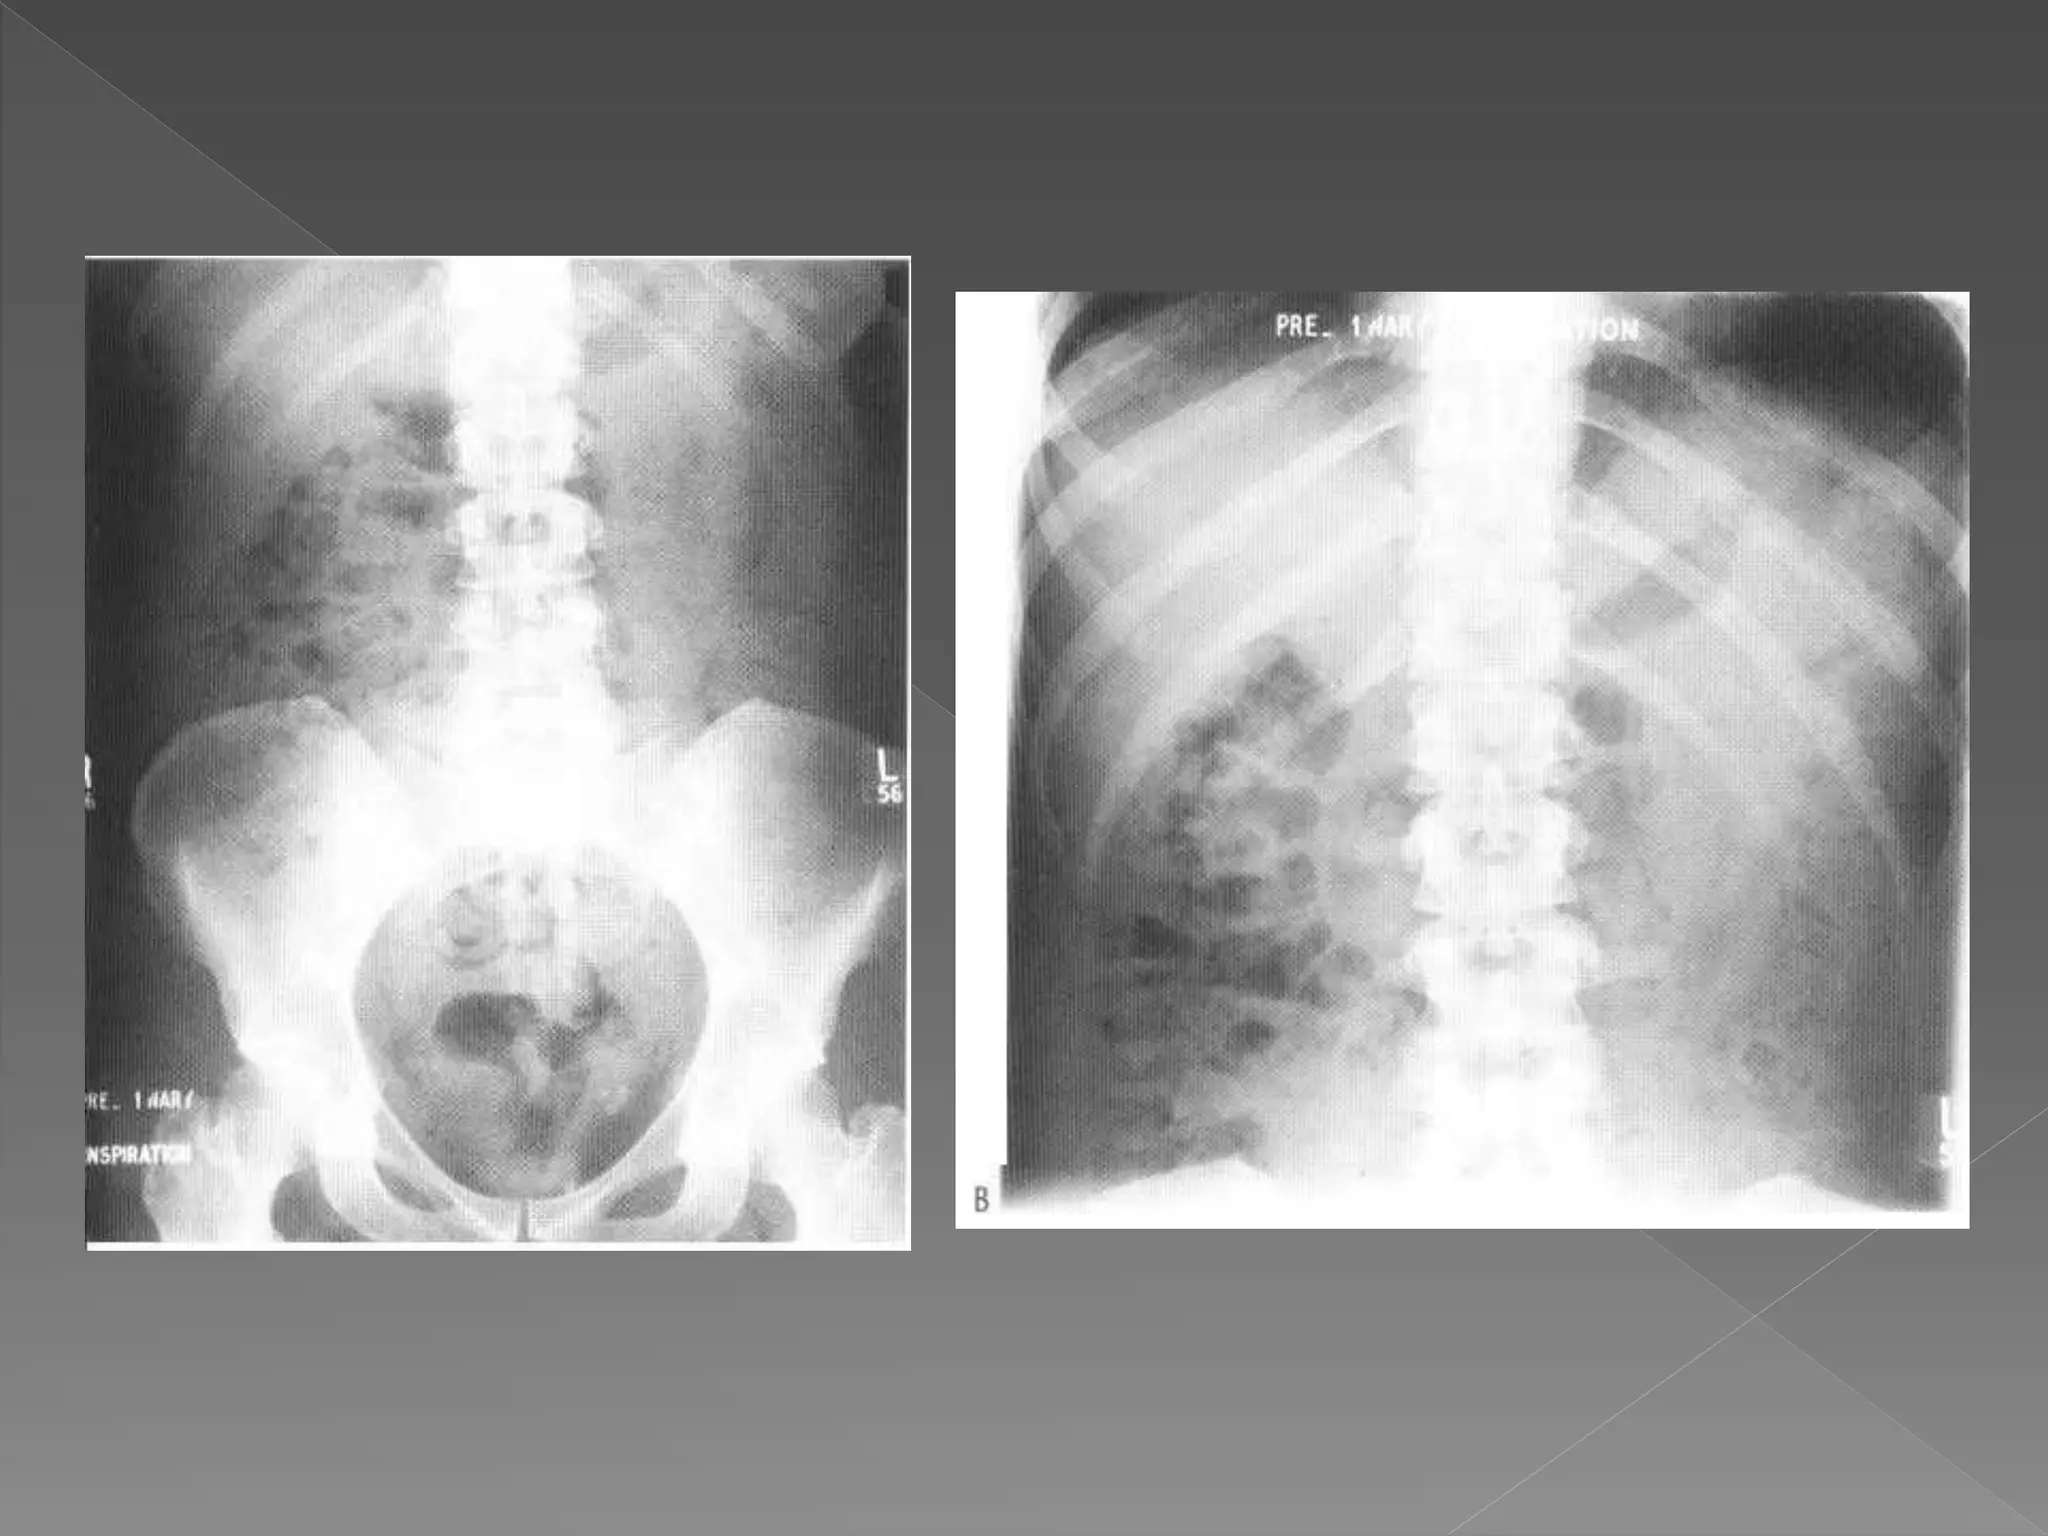

 The plain film demonstrates

 The plainfilm demonstrates calcification within distended upper pole calyces